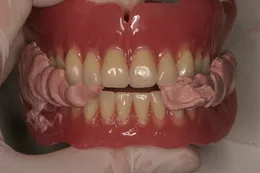

オーバーデンチャー

オーバーデンチャーとは、残り少なくなった歯牙の歯根を温存して入れ歯の支えにする方法のことです。最近ではインプラントも使われるようになりました。総入れ歯よりも安定性に優れ、「咬みごたえ」も感じることができます。

オーバーデンチャーも設計が重要になってきます。支えになるインプラントや歯根の配置や上下の咬み合わせを配慮した設計が必要です。また、メンテナンスも非常に大切です。

当院では総入れ歯から全顎のインプラントまで手掛けているのでオーバーデンチャーの診査から治療まで安心して受けていただけます。

(磁性アタッチメントを使用したオーバーデンチャー。義歯の真ん中を抜いてもしっかりとフィットしています)

(特殊な樹脂を応用したロケーターアタッチメントを使用したオーバーデンチャー。

MRI検査等を行われている患者様でも使用可能です。)